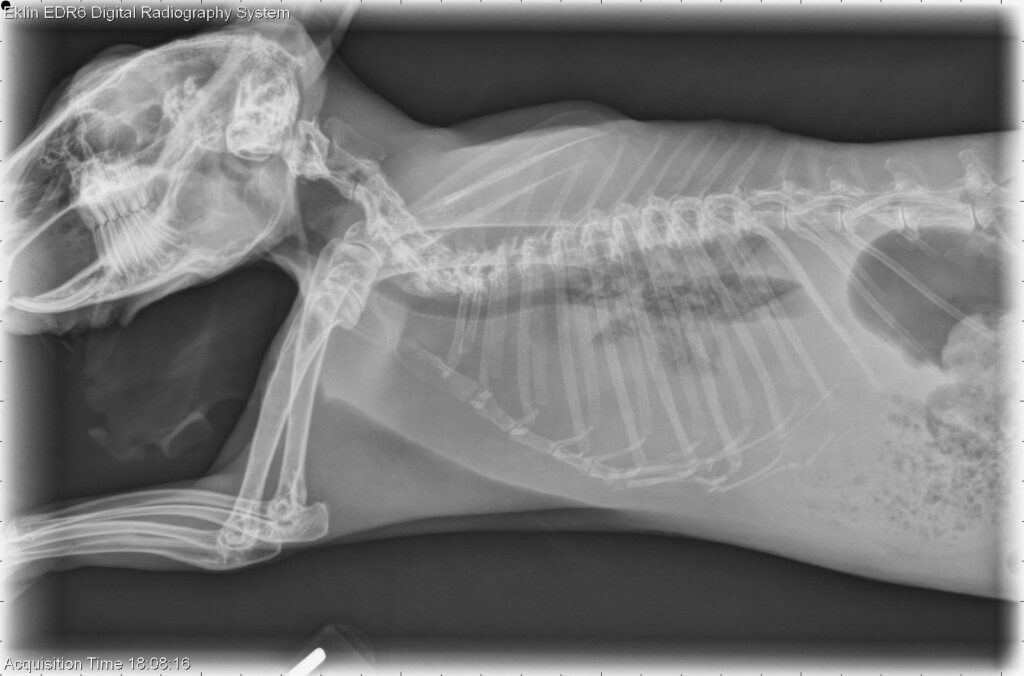

As already noted, a rabbit’s heart problem may not be evident to the caregiver. It may be during a routine evaluation, while the rabbit is sedated for some other procedure, or in a radiograph (X-ray) of the chest that the veterinarian notices an abnormal heart or lung sound or appearance. Sometimes it is a secondary condition that leads to the diagnosis of cardiac disease. Dr. Stewart Colby adds this from his experience:

When a rabbit presents with any respiratory issue or has abnormal lung or heart sounds, I usually begin diagnostics with radiographs. In many cases, heart issues are first noticed on radiographs taken for other reasons, such as gastrointestinal (GI) problems. Blood work, including for thyroid function, is also performed. Depending on the findings, electrocardiography (ECG) and ultrasound are the next step in diagnosing a particular issue, especially if medications are to be prescribed.

I do the initial work-up and, depending on the need, obtain additional information from electrocardiography (ECG, read by a cardiologist to help analyze abnormal sounds or rhythms), echocardiograms (ultrasounds, performed by a radiologist or cardiologist to help evaluate structural and functional abnormalities), or thoracic (chest) radiographs. The latter test helps determine the size and shape of the heart, lung concerns, or the presence of a tumor of the thymus (thymoma) that may present with clinical signs similar to heart disease.